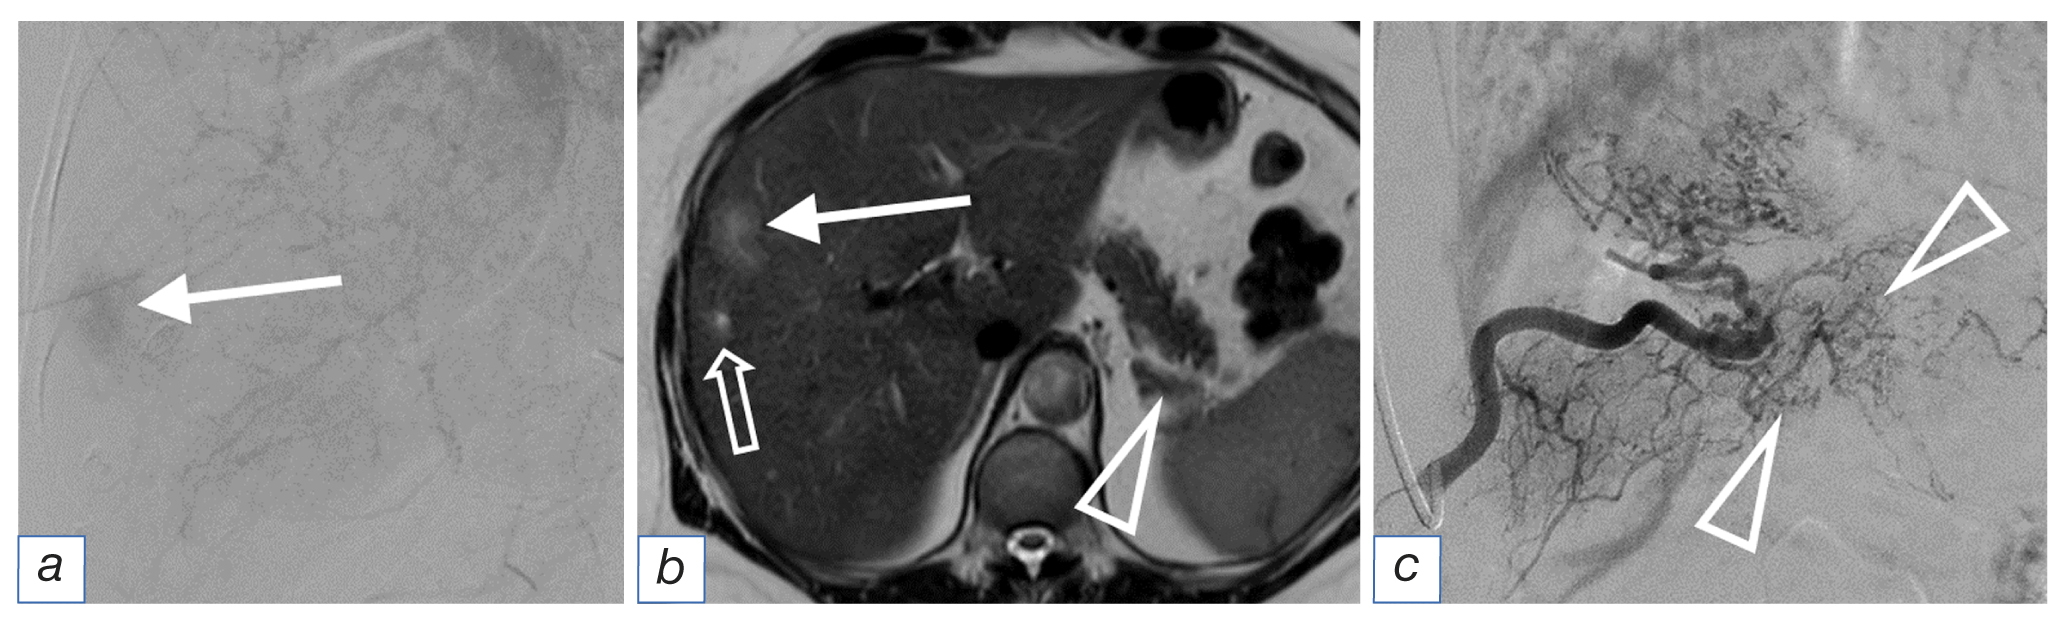

The angiographic image obtained during surgery was diverse. In some cases, we observed intense contrast of the metastasis parenchyma with a branched network of afferents (Fig. 2), whereas adjacent foci were only detected by recalibrated vessels originating in an atypical location (Fig. 3). In several observations, no angiographic signs of the tumor were observed. In such cases, the radiologist could only rely on the data from the diagnostic methods. The angioarchitectonics of the main tumor did not match the angiographic picture of liver metastases.

Fig. 2. Angiography (а): intense contrast of a metastasis with a diameter of 3 cm (white arrow); magnetic resonance imaging (b): the same metastasis with a diameter of 3 cm with slit necrosis in the structure (long arrow), an infiltrative metastasis with a diameter of 0.5 cm with a locally expanded bile duct in the center (3D arrow), the pancreatic tail tumor (triangular arrow); angiography of the pancreatic tumor (c): branched network of afferents (triangular arrows).

Foci <1 cm in diameter appeared as soft tissue substrate or infiltration zones, often with a locally dilated bile duct in the center (Fig. 2). These foci were typically detected on MRI and were not visible on angiography. However, eventually, they either disappeared or increased in size and transformed into the categories of metastases described previously.